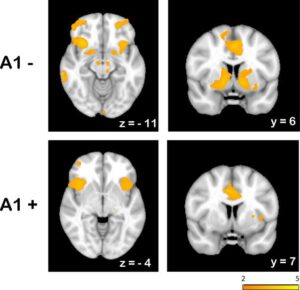

In a more recent study by the same researchers, 28 German males performed a similar learning task except partway through the experiment the “correct” choice was reversed – the one that used to be right was now wrong. The scientists found that people with at least one A at had a hard time consistently choosing the “correct” response after the reversal even if they had just chosen and been rewarded for that response. Perhaps not surprisingly, the behavior seemed to correlate with differences in brain activity. The researchers imaged the participants’ brains (with functional magnetic resonance imaging, or fMRI) while they performed the task and saw more signal in GG individuals (A1- in the figure) compared to AG and AA people (A1+ in the figure) in parts of the striatum and ventral midbrain where dopamine receptors are located. A similar correlation between reduced brain activity in dompinergic regions of the brain and impaired ability to “learn from mistakes” was also observed in the original study. Figure from: J Neurosci. 2009 March 25; 29(12): 3695—3704.